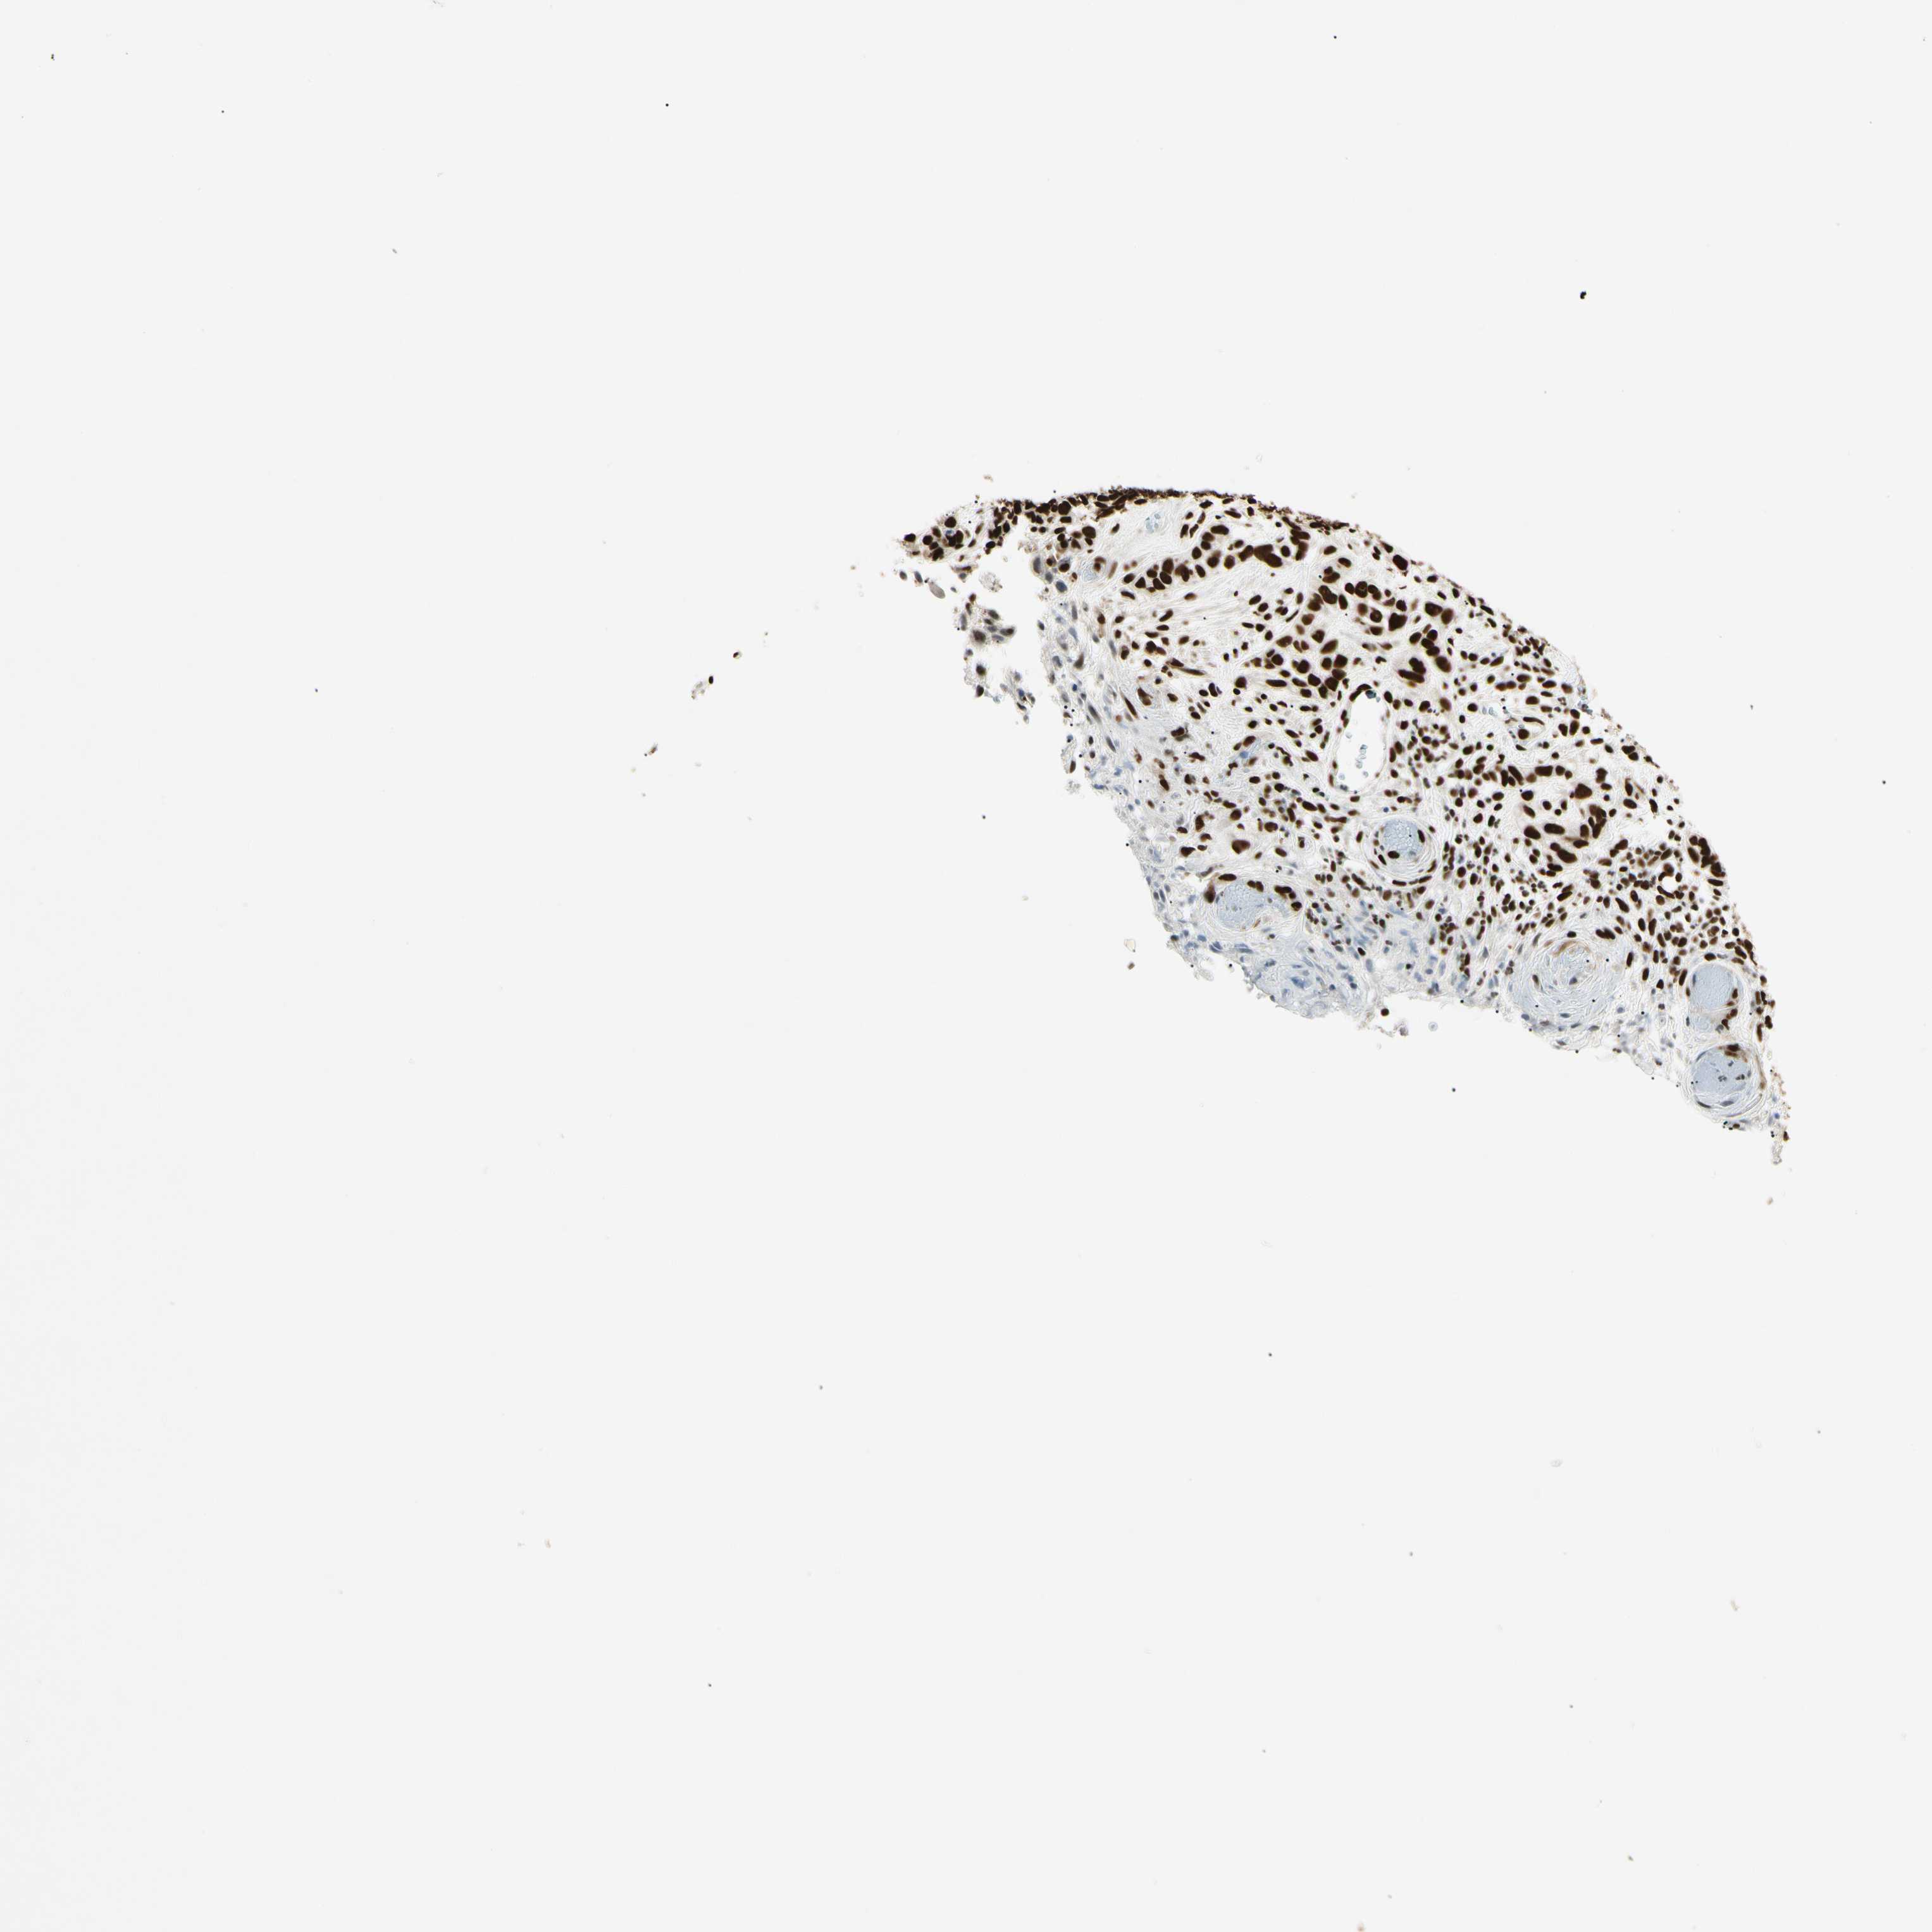

SKIN CANCER - Protein expressioni

A mouse-over function shows sample information and annotation data. Click on an image to view it in a full screen mode. Samples can be filtered based on level of antibody staining by selecting one or several of the following categories: high, medium, low and not detected. The assay and annotation is described here.

Antibody staining in the annotated cell types in the current human tissue is reported as not detected, low, medium, or high, based on conventional immunohistochemistry profiling in selected tissues. This score is based on the combination of the staining intensity and fraction of stained cells.

Each image is clickable and will lead to virtual microscopy that enables deeper exploration of all samples and also displays staining intensity scores, fraction scores and subcellular localization as well as patient and tissue information for each sample.

Antibody HPA008784

Staining

High

Intensity

Strong

Quantity

Location

Squamous cell carcinoma, NOS